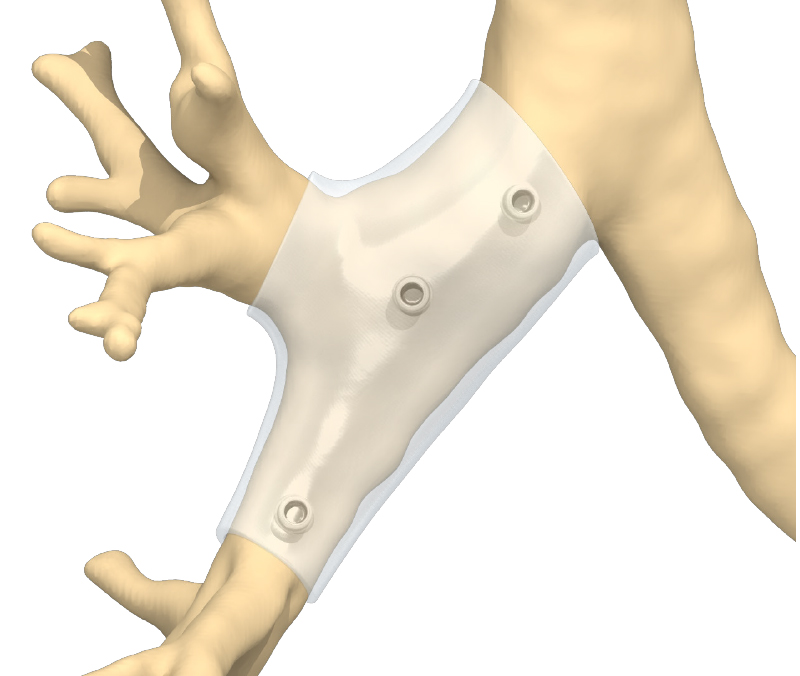

Auf der Grundlage der CT-Daten erstellen die Ingenieure einen Designvorschlag für den Stent.

Anhand des volumetrischen Bildes der betroffenen Atemwegsregion definiert der Arzt einen perfekt passenden Silikonstent. Der Stent wird virtuell entworfen und exakt an die Anatomie des Patienten angepasst. Der Arzt erhält eine interaktive 3D-Pdf mit dem vorgeschlagenen Stent-Design per E-Mail oder Download.

Ein interaktives Dokument (3D-Pdf) ermöglicht eine eingehende Analyse des vorgeschlagenen Stentdesigns.

Das interaktive 3D-Pdf dient dem Arzt als Analyseinstrument. Es veranschaulicht die Anatomie des Patienten und zeigt den vorgeschlagenen Stent innerhalb der Anatomie des Patienten. Durch die Möglichkeit, den Stent aus allen Perspektiven zu betrachten und Abstände und Wandstärken zu messen, kann der Arzt eine fundierte Entscheidung über die Eignung des Stentdesigns treffen. Sobald das Stentdesign abgeschlossen ist, gibt der Arzt seine Freigabe zur Herstellung des Novatech® 3D Stents.